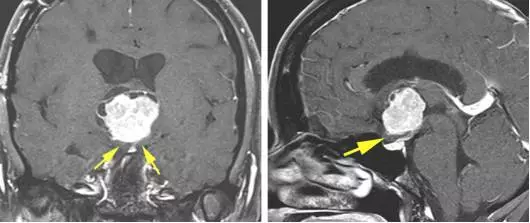

图2. 图示一例三脑室前部鞍上脊索样胶质瘤。该病例既往在其他医疗机构采用经额叶皮层入路手术。因为该手术入路的工作角度受限,最后不得不放弃全切。笔者在离断透明隔静脉后采用了经胼胝体-经扩大室间孔-经静脉入路最后分离并切除了前方脊索样组织。注意视交叉位于肿瘤下方(黄色箭头)和经终板的狭小空间。这些特点限制了经鼻和经额下手术入路。